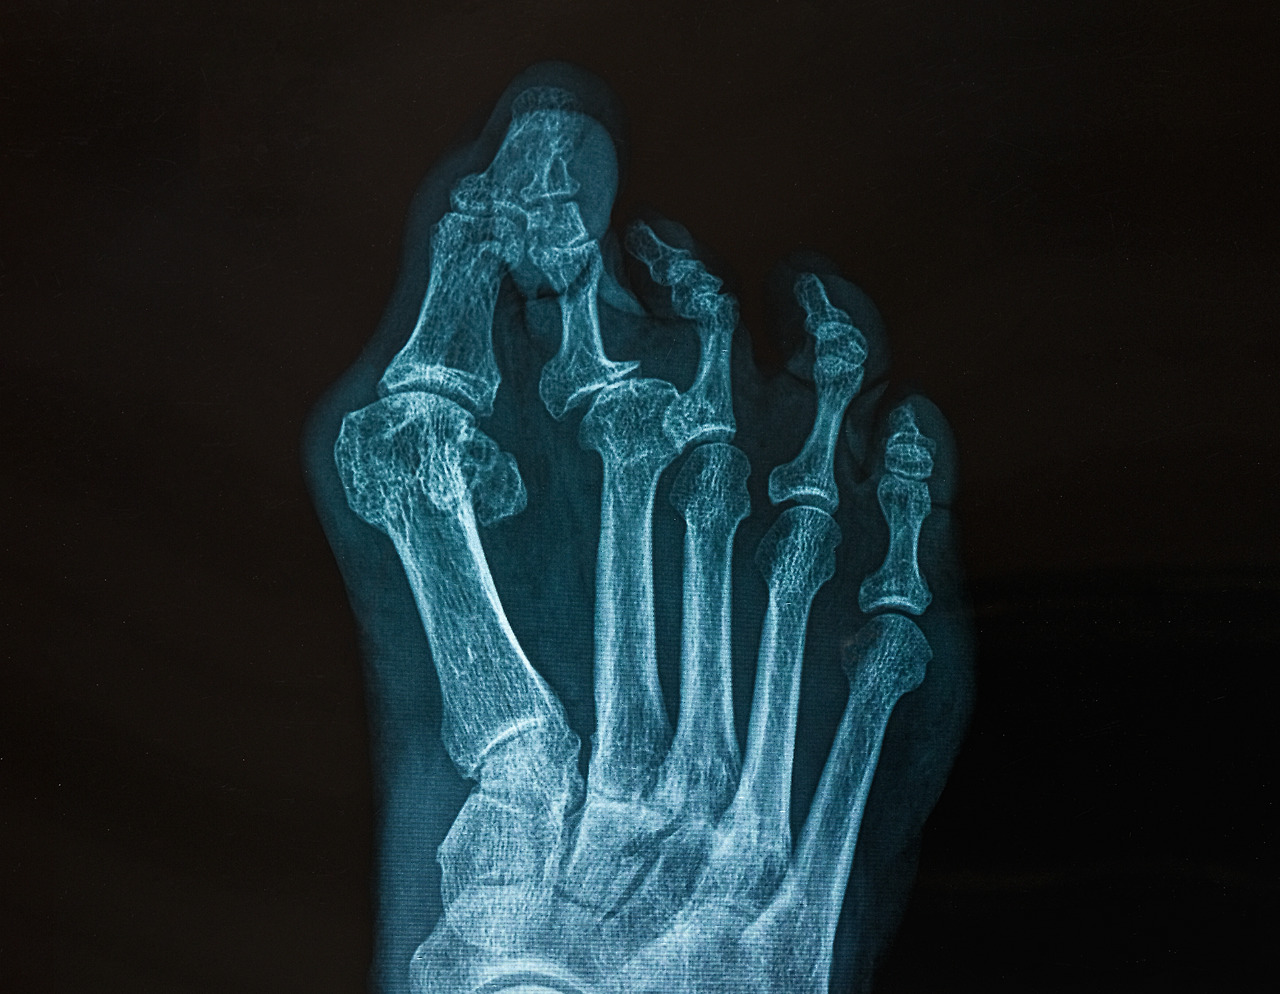

지간신경종은 발등뼈인 중족골 사이를 연결하는 인대가 어떤 요인에 의해 두꺼워지면서 발가락으로 가는 신경을 압박해 통증과 저림 증상을 유발하는 질환입니다.

발의 앞부분인 2-3-4번째 발가락 사이에 주로 발생하는 지간신경종은 무지외반증과 함께 대표적인 족부질환 중 하나인데요. 여성에서 발생률이 높다는 점에서 짐작할 수 있듯이 지간신경종원인은 발에 꽉 맞는 구두의 장시간 착용이 주원인이랍니다.

오진철 원장님“발가락으로 가는 신경이 두꺼워지는 지간신경종은 보행 중 발이 지면에서 들리는 경우처럼 발가락으로 가는 신경이 발허리뼈 사이의 인대와 발바닥 사이에서 반복적으로 늘리면서 발생하는 질환입니다. 따라서 자연스러운 발가락의 상태가 아니라 높은 굽과 좁은 발 볼로 과하게 젖혀지는 구두를 신을 경우에는 발가락에 있는 수많은 인대와 뼈 사이에 있는 신경이 눌릴 가능성이 높아지지요”라고 너무도 예쁜 구두가 지간신경종원인이 되는 이유를 자세히 설명해 주셨습니다.

덧붙여 발이 안쪽으로 휘어있거나 잘못된 보행습관, 그리고 중족지골간 인대 비후나 결절종, 지방종, 무지외반증 등도 지간신경종원인입니다.